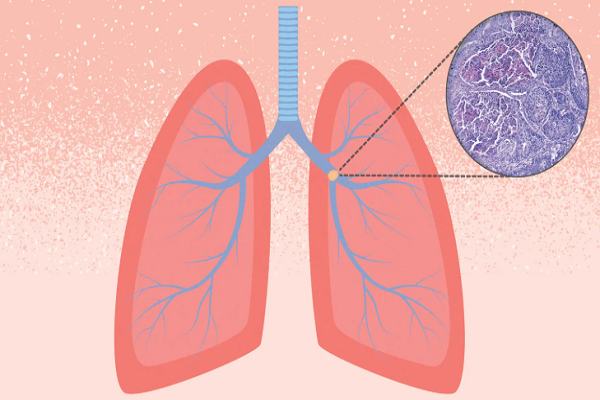

લિક્વિડ બાયોપ્સી શું છે, તે ફેફસાંના કેન્સરની સારવારને કેવી રીતે સરળ બનાવે છે

ફેફસાંનું કેન્સર ભારતમાં સૌથી ઘાતક રોગોમાંનું એક છે, પરંતુ હવે દર્દીઓને નવી લિક્વિડ બાયો બાયોપ્સી તકનીકને કારણે વારંવાર થતી પીડાદાયક સર્જરી અને જટિલ પ્રક્રિયાઓમાંથી રાહત મળવાની આશા છે. આ એક નોન-ઇન્વેસિવ ટેસ્ટિંગ પદ્ધતિ છે જેમાં ફક્ત લોહીના નમૂના લઈને કેન્સરની ઓળખ કરવામાં આવે છે. તો આજે વિશ્વ ફેફસાના કેન્સર દિવસ નિમિત્તે, અમે તમને જણાવીશું કે આ ટેકનોલોજી કેન્સરની સારવારમાં કેવી રીતે ક્રાંતિ લાવી રહી છે.

સૌથી મોટો પડકાર ફેફસાના કેન્સરને મોડેથી શોધવાનો છે.

નેશનલ ઇન્સ્ટિટ્યૂટ ઓફ હેલ્થના 2025ના અહેવાલ મુજબ, ભારતમાં કેન્સરના કુલ કેસોમાં ફેફસાના કેન્સરનો હિસ્સો 5.9 ટકા છે. જ્યારે તેના કારણે મૃત્યુ દર 8.1 ટકા છે. ડોકટરોના મતે, સતત ઉધરસ, થાક અથવા છાતીમાં દબાણ જેવા શરૂઆતના લક્ષણોને સામાન્ય રીતે અવગણવામાં આવે છે. જ્યારે તમે હોસ્પિટલ પહોંચો છો, ત્યારે કેન્સર શરીરમાં ફેલાઈ ચૂક્યું હોય છે, જેના કારણે સારવાર મુશ્કેલ બની જાય છે.

પરંપરાગત બાયોપ્સી હંમેશા શક્ય નથી.

અત્યાર સુધી, કોલોનના કેન્સરનું નિદાન કરવા માટે ટીશ્યુ બાયોપ્સીનો ઉપયોગ કરવામાં આવતો હતો. આમાં, ગાંઠમાંથી ટીશ્યુ દૂર કરવામાં આવે છે અને તેની તપાસ કરવામાં આવે છે. પરંતુ ક્યારેક ગાંઠ ફેફસાના એવા ભાગોમાં હોય છે જ્યાં પહોંચવું મુશ્કેલ હોય છે અને આ પ્રક્રિયા વૃદ્ધ લોકો, હૃદય અથવા ડાયાબિટીસના દર્દીઓ માટે જોખમી બની શકે છે. આ ઉપરાંત, એકવાર લેવામાં આવેલી બાયોપ્સી હંમેશા ગાંઠ વિશે સંપૂર્ણ માહિતી આપતી નથી.

લિક્વિડ બાયોપ્સી એ સર્જરી વિના પરીક્ષણ માટેનો એક વિકલ્પ છે.

લિક્વિડ બાયોપ્સી એ એક આધુનિક અને ઓછી જટિલ તકનીક છે જેમાં દર્દીના લોહીનું પરીક્ષણ કરીને જાણવામાં આવે છે કે કેન્સર સંબંધિત આનુવંશિક વિકૃતિઓ અથવા ગાંઠના ડીએનએ તેમાં હાજર છે કે નહીં. આનાથી દર્દીઓને રાહત તો મળે છે જ, સાથે સાથે ડોક્ટરોને કેન્સરની આનુવંશિક પ્રોફાઇલ સમજવામાં પણ મદદ મળે છે. ખાસ વાત એ છે કે આ ટેકનિક ભારતીય દર્દીઓમાં સામાન્ય રીતે જોવા મળતા જનીન પરિવર્તનોને ઓળખી શકે છે. આનાથી ડોકટરો લક્ષિત ઉપચાર શરૂ કરી શકે છે, જે પરંપરાગત કીમોથેરાપી કરતાં વધુ અસરકારક સાબિત થઈ શકે છે.

સારવાર દરમિયાન પણ દેખરેખ રાખી શકાય છે

લિક્વિડ બાયોપ્સીની બીજી ખાસિયત એ છે કે સારવાર દરમિયાન તેને ઘણી વખત પુનરાવર્તિત કરી શકાય છે. આનાથી ડોકટરો જાણી શકે છે કે દર્દીનો રોગ કેવી રીતે પ્રતિક્રિયા આપી રહ્યો છે અને ગાંઠ દવાઓ સામે પ્રતિરોધક બની રહી છે કે નહીં. જો આવું થાય તો ડૉક્ટર તાત્કાલિક સારવારની દિશા બદલી શકે છે.